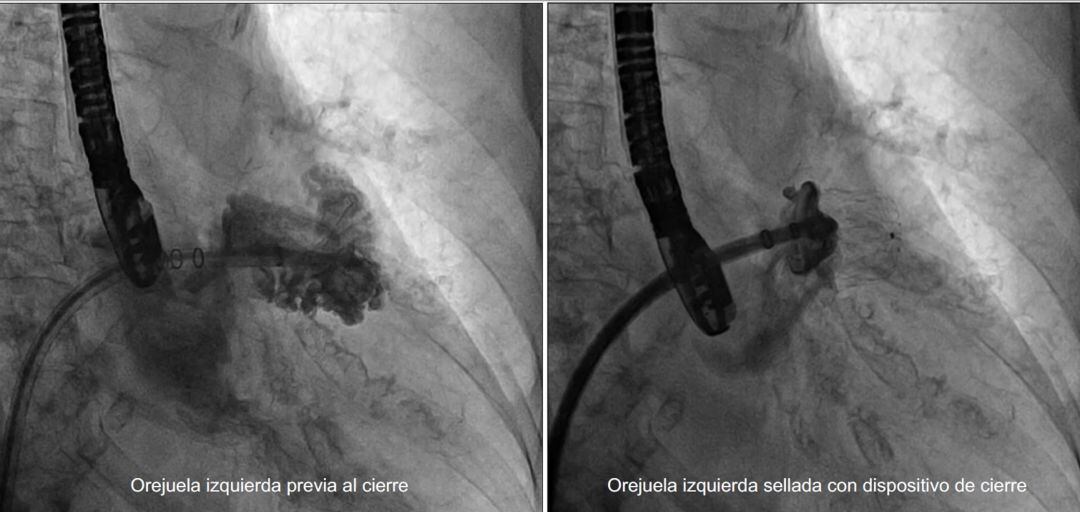

Cierre percutáneo de orejuela izquierda / Quirónsalud

El hospital Quirónsalud Valencia ha realizado un cierre percutáneo de orejuela izquierda, intervención pionera en la sanidad privada valenciana. Gracias a esta técnica, a través de una simple punción venosa femoral, el cardiólogo intervencionista es capaz de cerrar mediante un dispositivo específico el apéndice o cavidad izquierda ubicada dentro del corazón denominado orejuela.

Esta técnica, mínimamente invasiva, se realiza bajo sedación y anestesia local a través de la vena femoral, gracias a la cual se alcanza el lado izquierdo del corazón y mediante la monitorización con ecografía y rayos X simultánea se posiciona un pequeño dispositivo en la puerta de esta cavidad con el que se asegura que está completamente sellada. Tras la intervención el paciente recibe el alta hospitalaria en las doce horas siguientes.